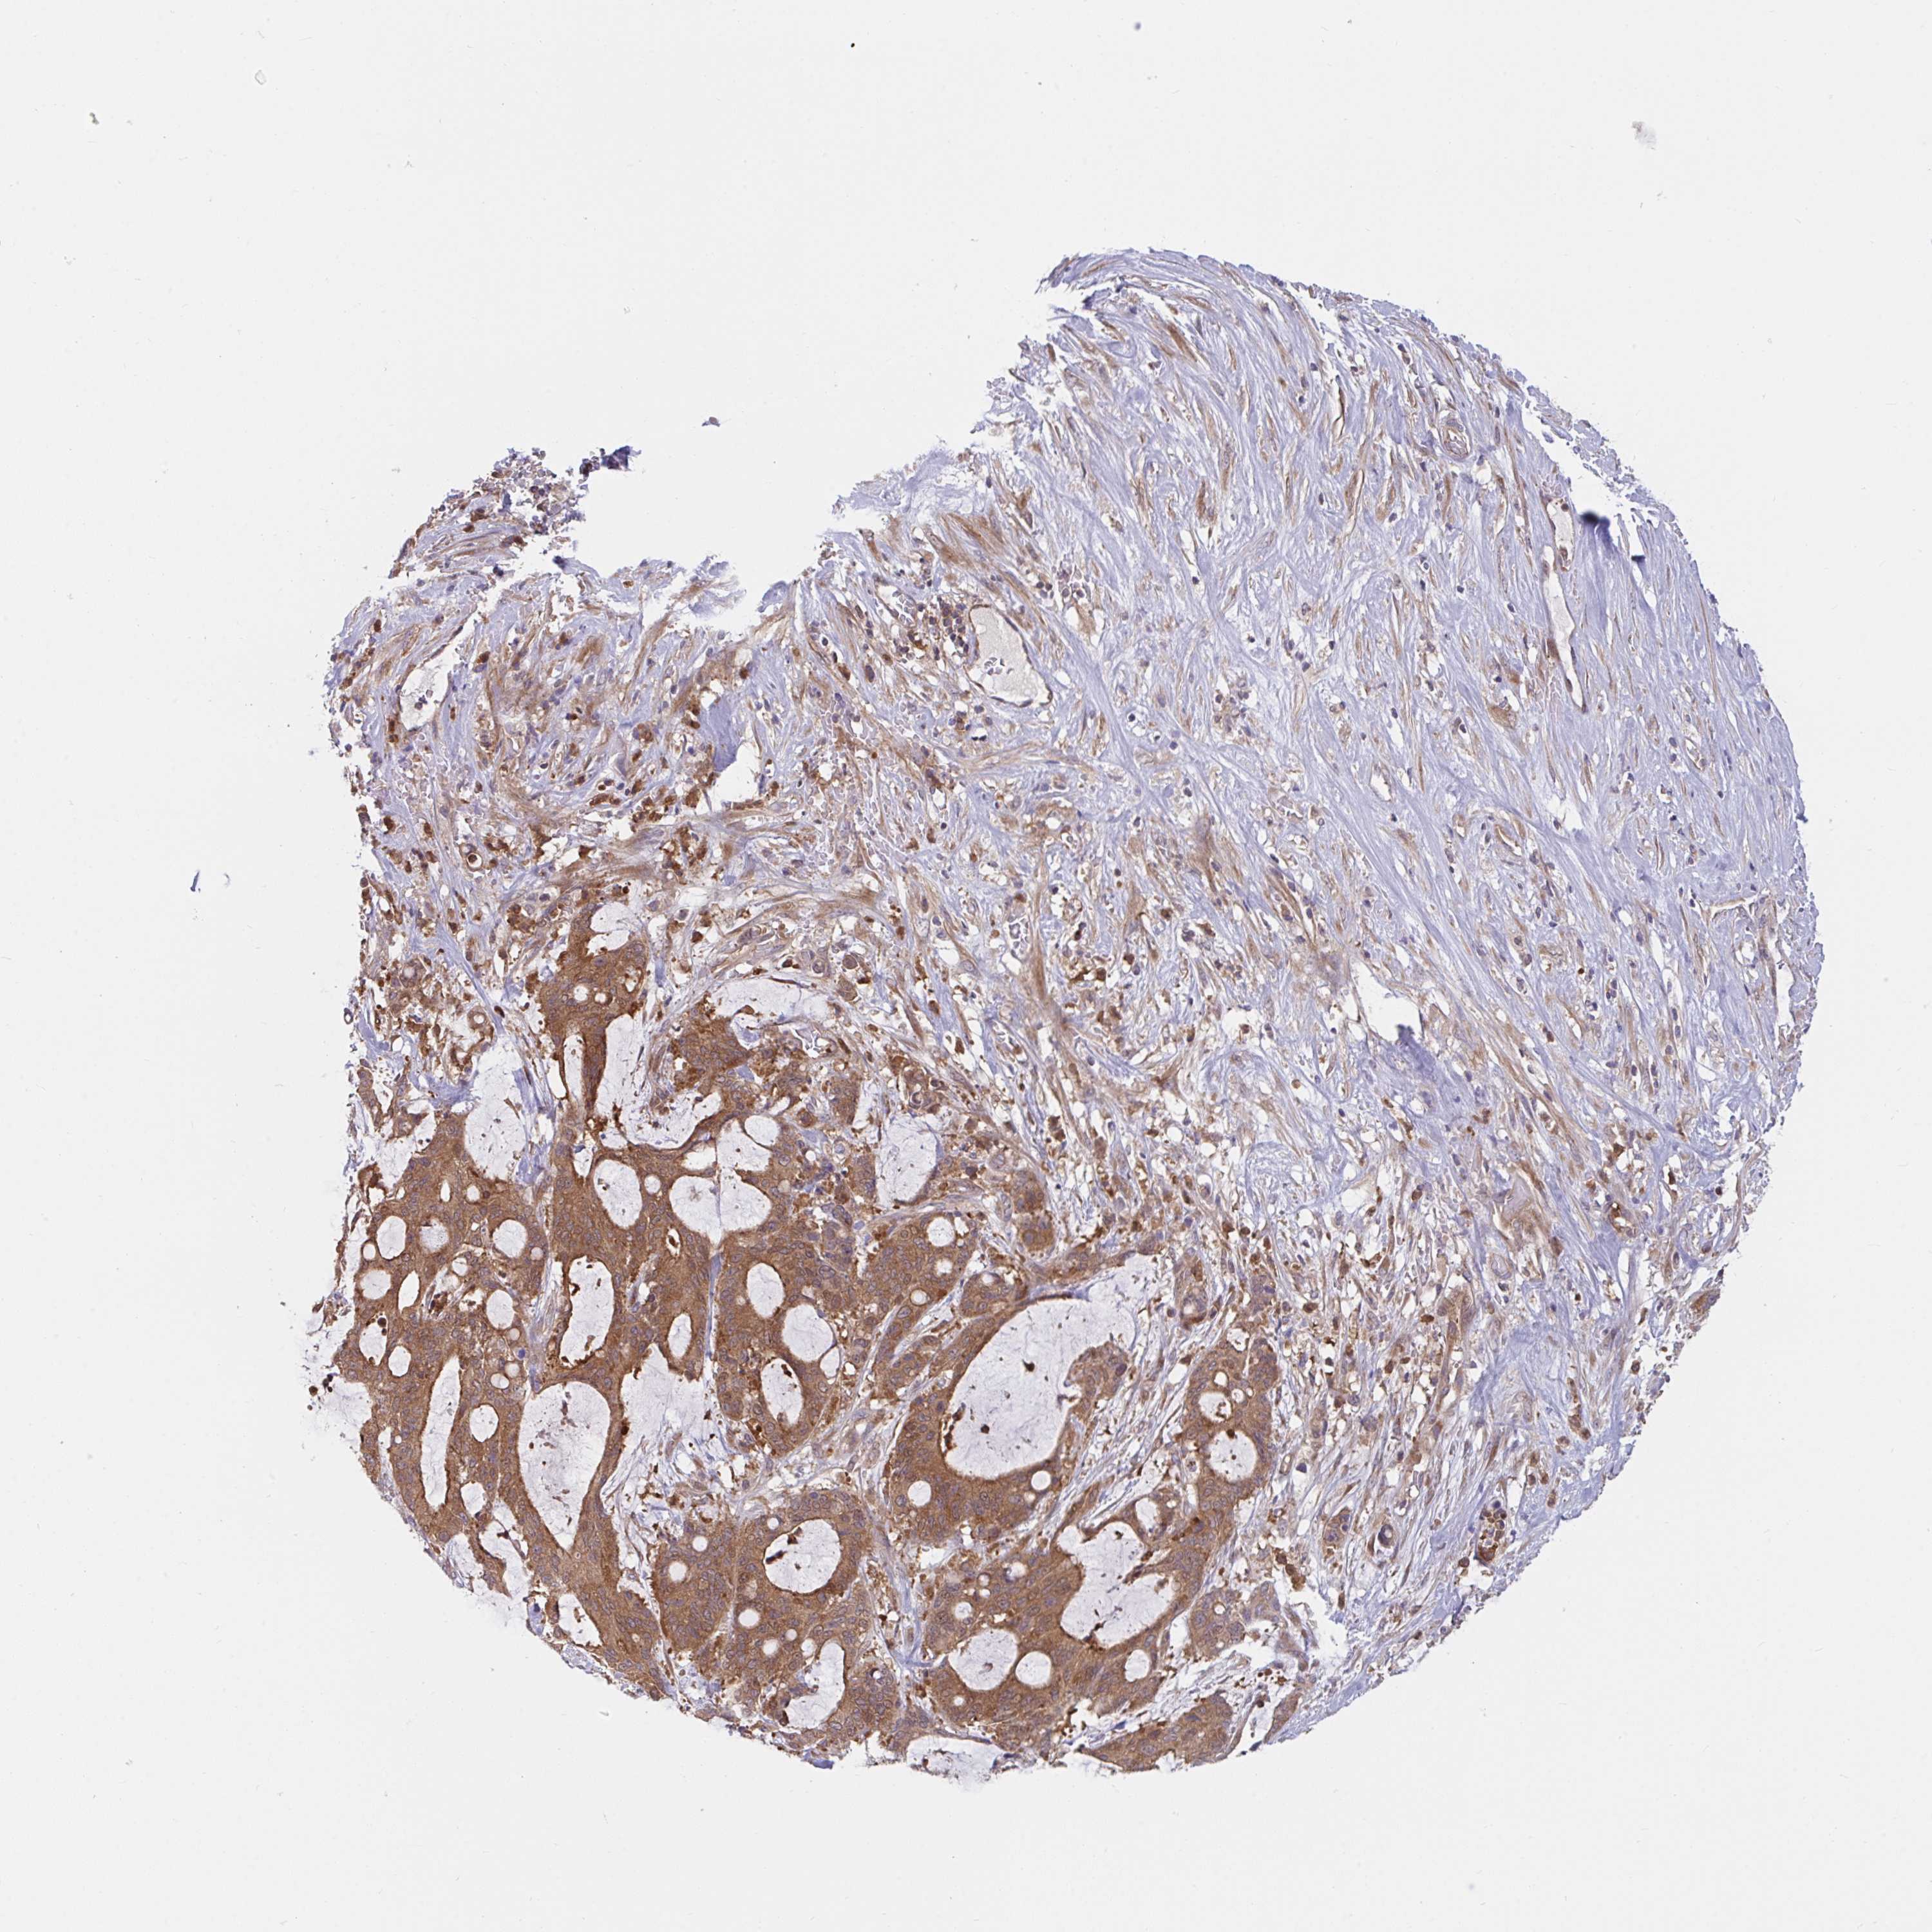

LIVER CANCER - Protein expressioni

A mouse-over function shows sample information and annotation data. Click on an image to view it in a full screen mode. Samples can be filtered based on level of antibody staining by selecting one or several of the following categories: high, medium, low and not detected. The assay and annotation is described here.

Note that samples used for immunohistochemistry by the Human Protein Atlas do not correspond to samples in the TCGA dataset.

Antibody stainingi

Antibody staining in the annotated cell types in the current human tissue is reported as not detected, low, medium, or high, based on conventional immunohistochemistry profiling in selected tissues. This score is based on the combination of the staining intensity and fraction of stained cells.

Each image is clickable and will lead to virtual microscopy that enables deeper exploration of all samples and also displays staining intensity scores, fraction scores and subcellular localization as well as patient and tissue information for each sample.

Antibody HPA058474

Staining

High

Medium

Low

Not detected

Intensity

Strong

Moderate

Weak

Negative

Quantity

>75%

75%-25%

<25%

None

Location

Nuclear

Cytoplasmic/membranous

Cytoplasmic/membranous,nuclear

Cholangiocarcinoma

Carcinoma, Hepatocellular, NOS